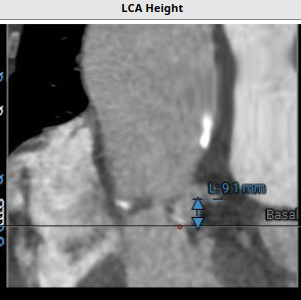

患者,女性,83岁,因“劳动过后呼吸困难多年,近一个月症状明显加重”入院,至中山医院经过详细的超声和CT诊断,发现其:主动脉瓣狭窄伴有关闭不全(反流),瓣叶增厚,游离缘中度钙化,同时左侧冠脉开口9.1mm稍低,二尖瓣环重度钙化,STS评分8.6。经过临床详细评估,计划植入一枚22mm的杰成经血管介入生物主动脉瓣膜。

患者术前CT分析:患者主动脉瓣为三叶式,瓣叶重度钙化伴增厚;左侧冠脉开口9.1mm稍低;主动脉弓角度偏小。

左冠高度